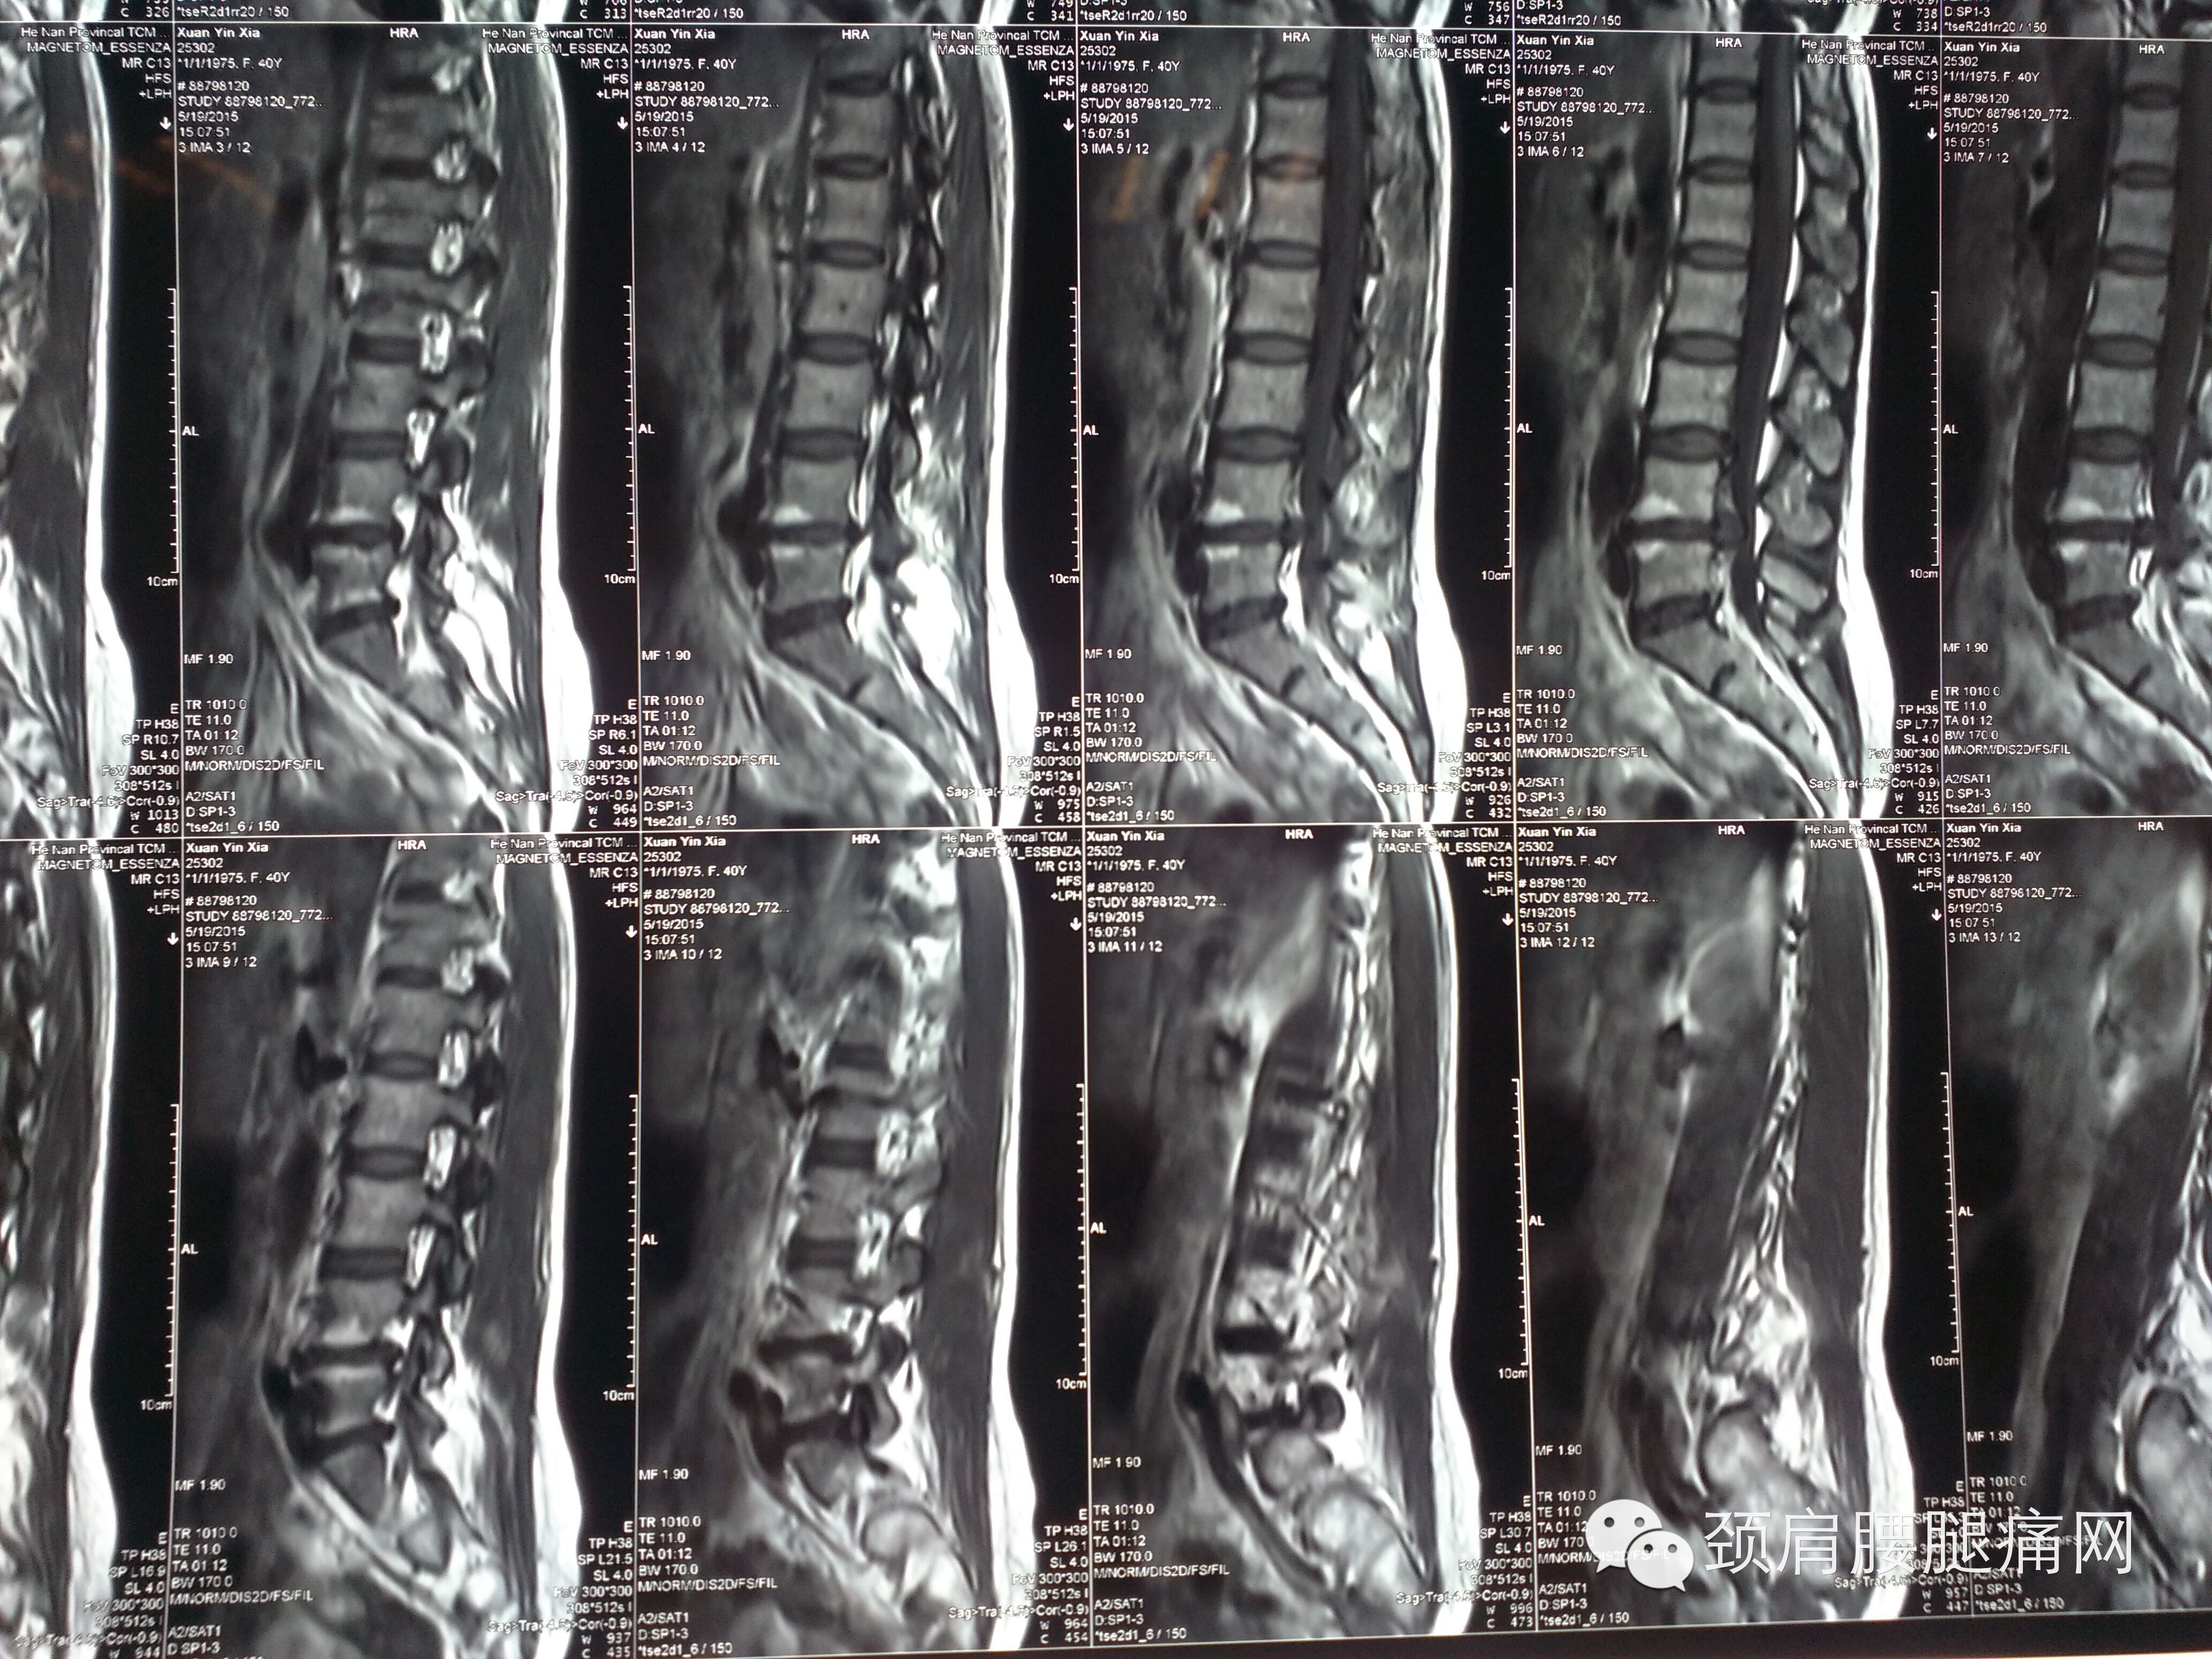

患者轩某某,女,41岁,以“左下肢麻木疼痛酸沉一月”为主诉来河南省中医院疼痛科就诊。

CT如图所示:L4-L5椎间盘突出(髓核脱出可能)

L3-L4、L5-S1椎间盘轻度突

MRI如图所示:L4-L5椎间盘突出(左旁中央型)

L3-L4轻度突出(中央型)